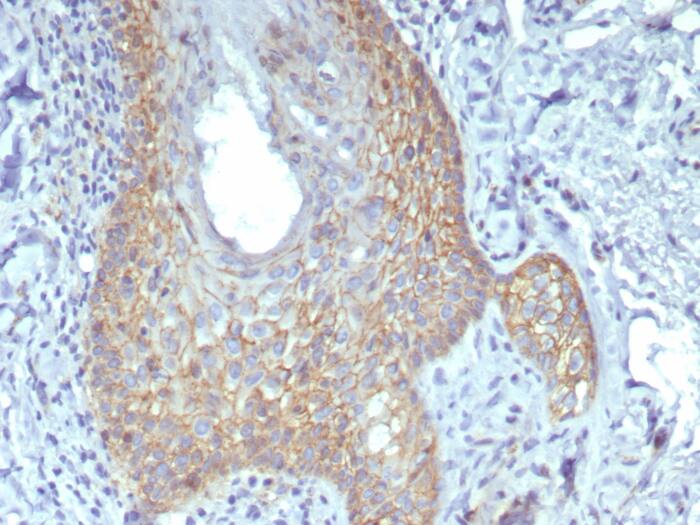

Formalin-fixed, paraffin-embedded human skin stained with beta-Catenin antibody (rCTNNB1/8043) - Azide and BSA Free. HIER: Tris/EDTA, pH9.0, 45min. Secondary: HRP-polymer, 30min. DAB, 5min.